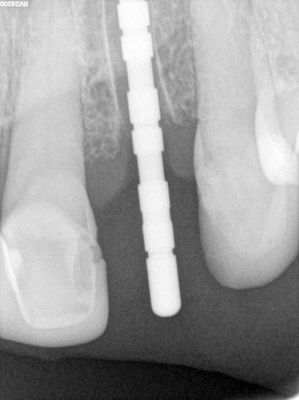

long root, atraumatic exo, loss of labial bone at apical end of socket, implant placed in ideal position, socket and buccal grafted with allograft and collagen membrane. Sutured prior to loading implant with screw-retained temp crown out of centric and protrusive occlusion